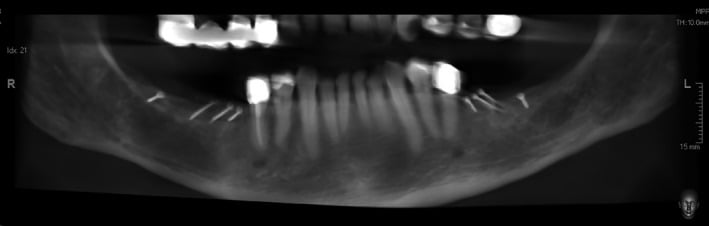

Figure 1.

Preoperative CBCT: vertical bone defects in the third and fourth quadrant

Figure 4.

CBCT before implantation: significant vertical bone gain after 4 months of healing in both quadrants